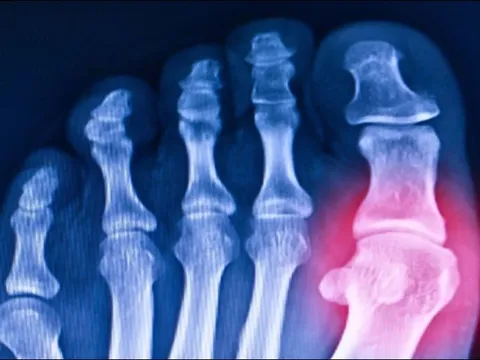

Các nhà khoa học ‘hồi sinh’ gen 20 triệu năm tuổi giúp chống lại bệnh gout

DNVN - Cơn đau do gout đã hành hạ con người suốt hàng thiên niên kỷ, nhưng bây giờ, các nhà khoa học đã đi ngược về quá khứ xa xưa hơn 20 triệu năm để khôi phục một loại gen có thể giúp điều trị căn bệnh này và những bệnh tương tự.